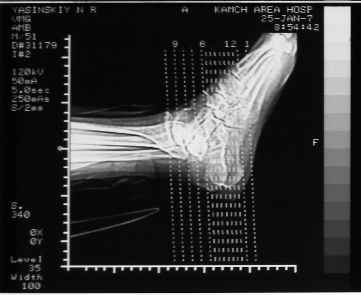

Уважаемые коллеги! Пришел на консультацию больной - "растяжение связок левого голеностопного сустава" полтора месяца назад, поскольку был в морях, на ногу не наступал. Снимки и КТ - в приложении.

Как бы кто лечил с учетом времени после травмы - 52 дня? Человек физического труда. Социальные запросы самого больного высокие, плюс медкомиссии перед рейсами - с хромотой нельзя!